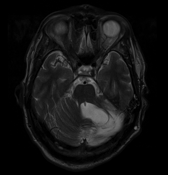

MRI2 January 23, 2015 By Gari Share this:TweetShare on Tumblr Email a link to a friend (Opens in new window) Email More Share on Reddit (Opens in new window) Reddit Print (Opens in new window) Print Like Loading... About Gari Northern lad; living out in the Peak District and rediscovering life after having had a brain tumour.